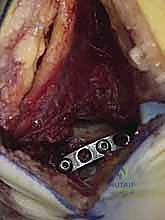

المرحلة الرابعة: التثبيت الداخلي (Internal Fixation)

بمجرد التأكد من أن العظم عاد لشكله الطبيعي تماماً، يتم استبدال الأسلاك المؤقتة بتثبيت دائم. يستخدم الدكتور هطيف أحدث الغرسات الطبية العالمية:

* مسامير التيتانيوم المجوفة (Cannulated Screws): مسامير قوية جداً يتم إدخالها عبر العظم لضغط أجزاء الكسر معاً.

* المسامير بدون رأس (Headless Compression Screws): تُستخدم في المناطق المغطاة بالغضروف، حيث تُدفن بالكامل داخل العظم لكي لا تحتك بالمفصل وتسبب تآكلاً.

* الشرائح المعدنية الدقيقة (Mini-Plates): تُستخدم أحياناً لتدعيم التثبيت في حالات التفتت الشديد (Comminution) حيث لا تكفي المسامير وحدها.

يتم وضع المسامير عادة من اتجاهين (من الأمام للخلف، ومن الخلف للأمام) لإنشاء هيكل ميكانيكي صلب يتحمل الضغوط.

المرحلة الخامسة: التحقق الإشعاعي الفوري والإغلاق

قبل إنهاء العملية، يستخدم الدكتور هطيف جهاز الأشعة السينية المتحرك داخل غرفة العمليات (C-arm Fluoroscopy) لأخذ صور متعددة والتأكد من:

1. المحاذاة المثالية للكسر.

2. عدم وجود أي فجوات أو درجات في السطح المفصلي.

3. الطول والموقع الصحيح للمسامير (للتأكد من أنها لا تخترق المفاصل المجاورة).